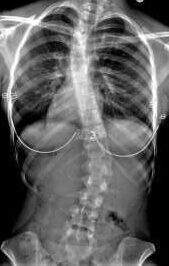

Scoliotic spine

Over our 53 years in healthcare seating, we’ve worked with thousands of clients with complex postural needs. The challenge has remained consistent: every spine with scoliosis or significant asymmetry presents differently, yet traditional seating solutions often rely on fixed custom moulds.

These one-off solutions, while necessary in many cases, come with limitations: extended lead times, significant costs, and inflexibility as needs evolve or conditions change.

For therapists working with severe scoliosis and complex spinal deformities, this means something practical: the ability to achieve truly individualised positioning without custom moulds or extended fabrication times.